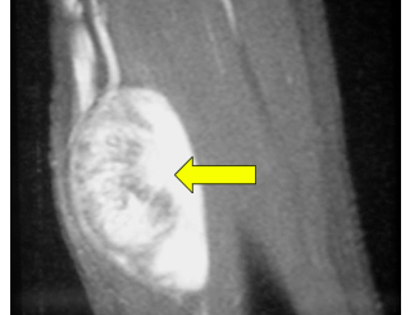

Pre-Op MRI of Tumor

This is an image of the tumor. The tumor is removed with margins ensuring that no tumor is left in the area.